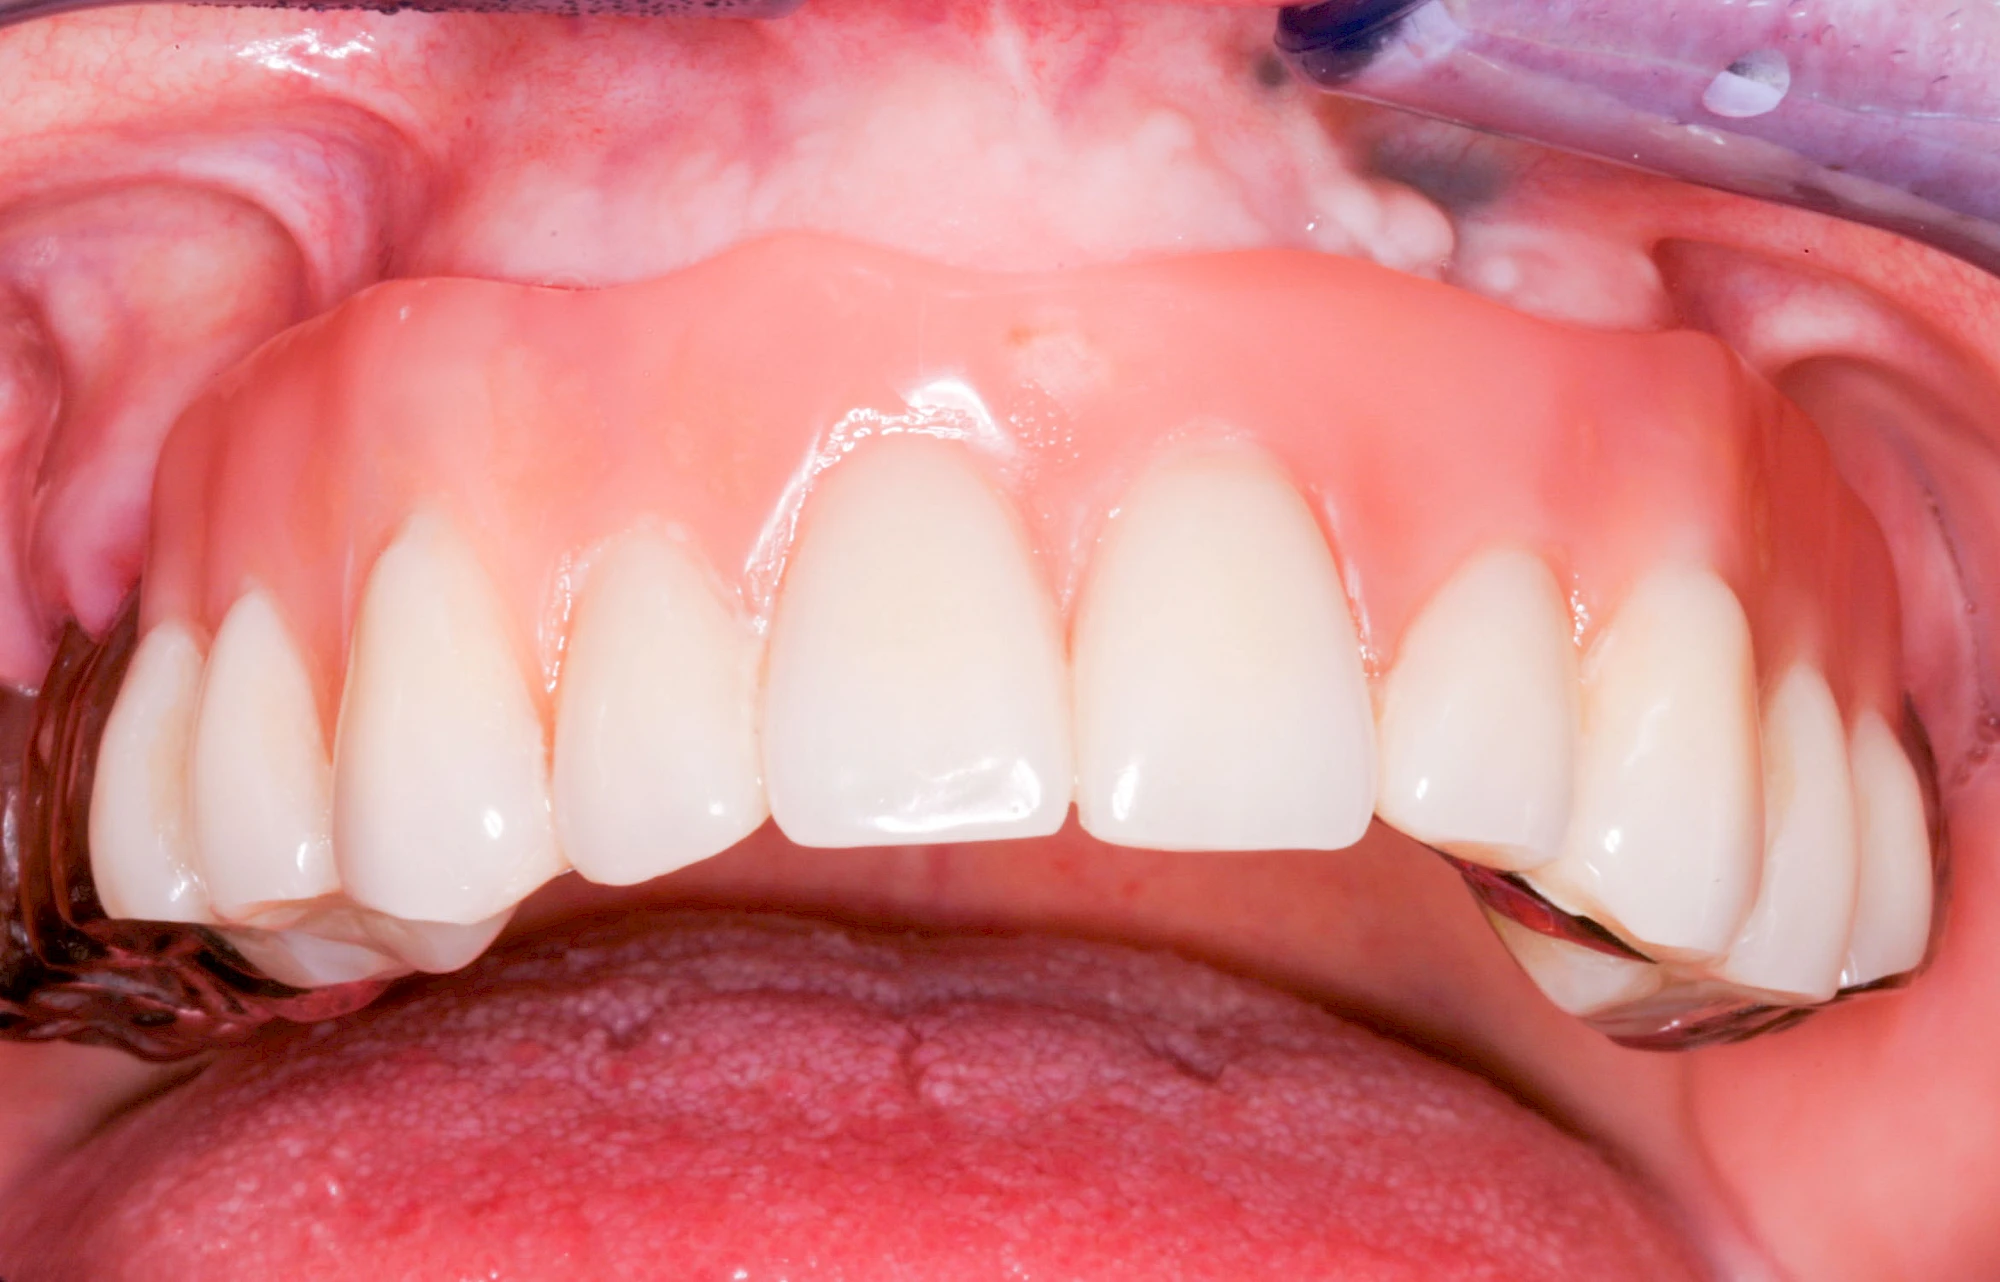

Sonderform: Wucherung

Epulis

Diese Vermehrung von Bindegewebe im Bereich des Zahnfleisches kann auf folgende Ursachen zurückgeführt werden:

- Nebenwirkung von Medikamenten: Immunsuppressiva (Cyclosporin A), Antihypertonika (Kalziumantagonisten/Kalziumkanalblocker: Nifedipin, Amlodipin sowie Diltiazem, Verapamil) und Antiepileptika (Phenytoin)

- Hormonschwankung im Rahmen der Schwangerschaft (Schwangerschaftsepulis)